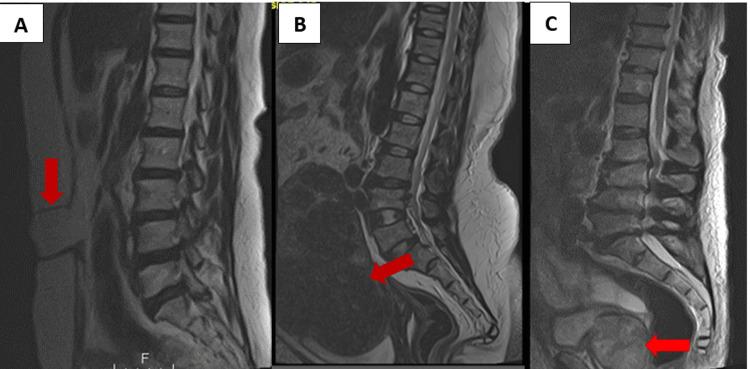

Background Extraspinal findings are commonly detected on magnetic resonance imaging of the lumbar spine, but these findings are sometimes omitted from radiological reports. Failing to report these findings could have a clinical impact on the patients. The purpose of this study was to determine the prevalence and reporting rates of extraspinal findings on lumbar spine magnetic resonance imaging. Methods Retrospective analysis was done on lumbar spine magnetic resonance images done at the Korle-Bu Teaching Hospital between January 2020 and December 2021. A total of 1267 patients underwent lumbar spine magnetic resonance imaging within the period. The degree of clinical significance of the extraspinal findings was ascertained using the computed tomography colonography reporting and data system classification scheme. The reporting rate was determined by referring to the archived radiological reports. Statistical analysis was done using IBM SPSS Statistics for Windows, Version 25 (Released 2017; IBM Corp., Armonk, New York, United States). Results A total of 737 extraspinal findings were detected from 530 patients. The overall reporting rate of extraspinal findings was 62.6% (461/737). The most common extraspinal finding was a simple renal epithelial cyst (n = 333). Clinically significant findings were detected in 107 out of the 530 patients; 36.4% of the clinically significant findings were not reported when compared with the archived reports. Conclusion Extraspinal findings on lumbar spine imaging were common in our study population. When radiologists are reporting lumbar spine magnetic resonance imaging, it is crucial to be aware of the risk of missing clinically significant findings.

背景 在腰椎磁共振成像中通常会检测到脊柱外的病变,但这些病变有时会在放射学报告中被遗漏。未报告这些病变可能会对患者产生临床影响。本研究的目的是确定腰椎磁共振成像中脊柱外病变的患病率和报告率。方法 对2020年1月至2021年12月在科勒-布教学医院进行的腰椎磁共振图像进行回顾性分析。在此期间共有1267例患者接受了腰椎磁共振成像检查。使用计算机断层结肠造影报告和数据系统分类方案确定脊柱外病变的临床意义程度。通过查阅存档的放射学报告来确定报告率。使用IBM SPSS Statistics for Windows,版本25(2017年发布;IBM公司,美国纽约州阿蒙克)进行统计分析。结果 从530例患者中检测到737处脊柱外病变。脊柱外病变的总体报告率为62.6%(461/737)。最常见的脊柱外病变是单纯性肾上皮囊肿(n = 333)。在530例患者中有107例检测到具有临床意义的病变;与存档报告相比,36.4%具有临床意义的病变未被报告。结论 在我们的研究人群中,腰椎成像中的脊柱外病变很常见。当放射科医生报告腰椎磁共振成像时,意识到遗漏具有临床意义病变的风险至关重要。